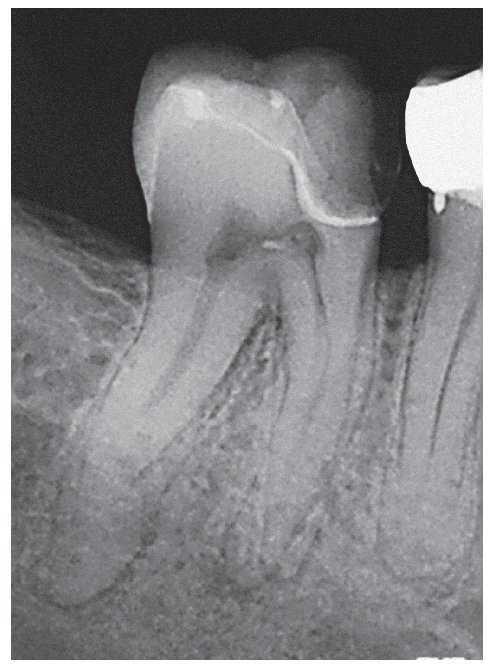

Figura 2a. La radiografía diagnóstica del diente 47 muestra una periodontitis apical postendodóntica.

Figura 2b. En sentido vestibular ya se observa un trayecto fistuloso.

Figura 2c. Situación después de la apertura cameral: la obturación existente carece de sellado marginal. No se identificó la luz del conducto radicular original. Alrededor del material de obturación se detecta tejido necrótico de aspecto negruzco, sobre todo en la zona distal donde el conducto radicular adopta una forma marcadamente ovalada. Se pasó por alto y no se preparó el istmo frecuentemente existente en los molares inferiores entre el conducto mesiovestibular y el conducto mesiolingual.

Figura 2d. Después de limpiar el suelo de la cámara pulpar salen a la luz las estructuras del sistema de conductos radiculares que se pasaron por alto en el primer tratamiento.

Figura 2e. Situación después del retratamiento de los conductos principales. Se aprecia con claridad el tejido existente en el istmo mesial.

Figura 2f. Situación después de la preparación completa del istmo mesial coronal. Se pudo palpar otro istmo en el tercio medio de la raíz mesial a través del que fluyó líquido de irrigación. Se preparó este istmo mediante instrumentos ultrasónicos.

Figura 2g. Situación después de la obturación termoplástica. Los istmos también muestran un buen sellado marginal.

Figura 2h. Radiografías de control después de la obturación: el tamaño de la luz obturada es considerablemente mayor en comparación con el tratamiento inicial. Se consiguió una obturación homogénea de los dos istmos situados en la parte coronal y apical de la raíz mesial.

Figura 2i. La radiografía de control realizada a los 12 meses mostró una curación ósea completa de la lesión apical.